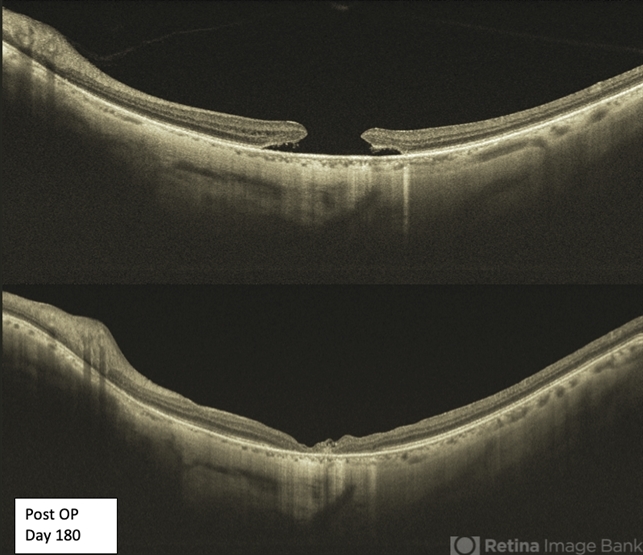

- Swept source OCT of a 65-yea-old patient with a large macular hole before and after surgery.